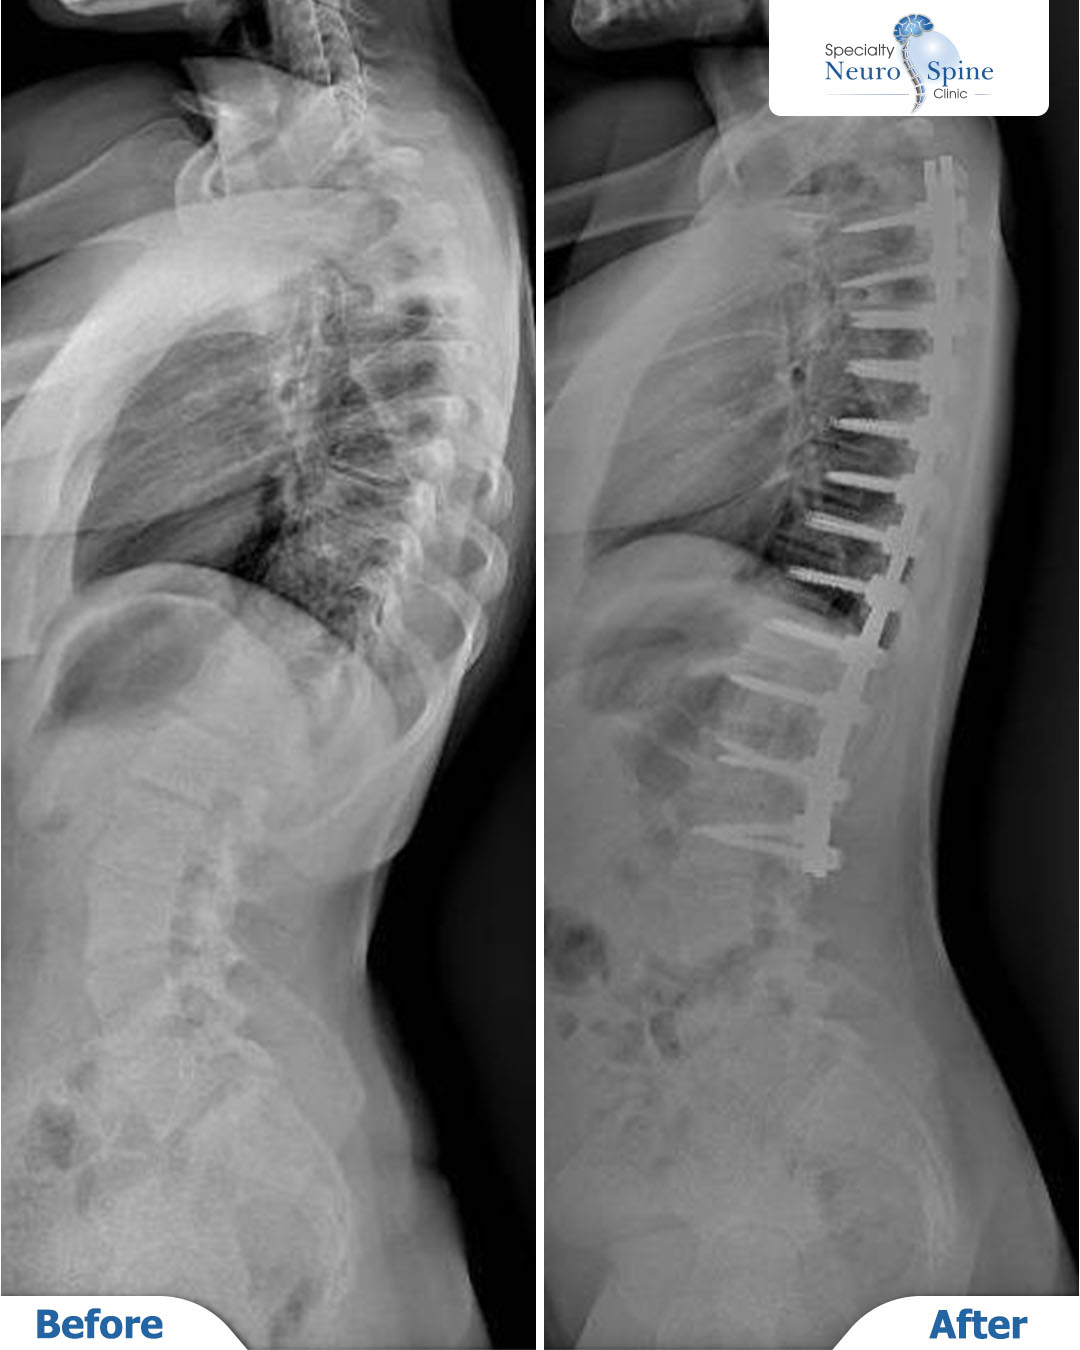

Before and after X-rays of our dear patient Mariam, a 16 years old from Jordan, who underwent spinal fusion surgery from the third thoracic vertebra (T3) to the second lumbar vertebra (L2) using advanced minimally invasive endoscopic techniques.